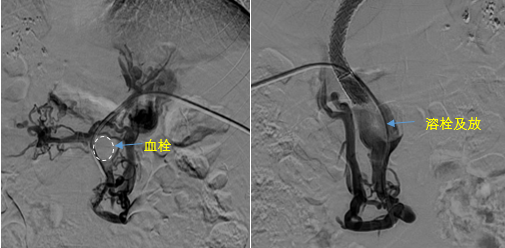

• 血栓攔路,如何破局——罕見巨大門靜脈血栓TIPS手術(shù)實錄

血栓攔路,如何破局——罕見巨大門靜脈血栓TIPS手術(shù)實錄

日前,西安國際醫(yī)學(xué)中心醫(yī)院消化病醫(yī)院為一位罕見巨大門靜脈血栓患者行TIPS手術(shù)。將患者體內(nèi)的“定時炸彈”拆除。9月份的一天,李女士晚飯后發(fā)覺惡心,嘔吐出鮮紅色的血塊,隨即又出現(xiàn)了黑便。在醫(yī)院檢查發(fā)現(xiàn)是食管胃底靜脈曲張破裂出血。……